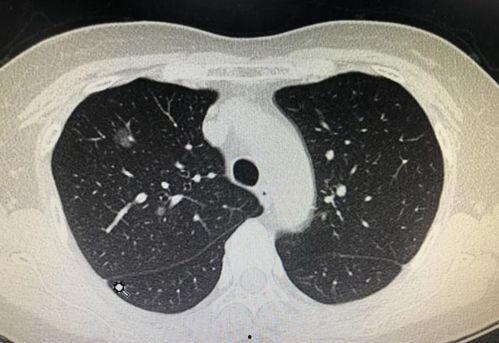

首先,得先弄明白什么是肺结节。肺结节,简单来说,就是肺部出现的小块阴影,通常直径小于3厘米。这玩意儿可能是由很多原因引起的,比如炎症、感染、肿瘤等。听起来是不是有点吓人?但别慌,大多数肺结节都是良性的,只有少数是恶性的。